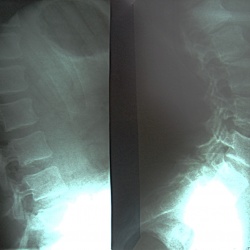

после тренировки почувствовала жалобы на резкие боли в области крестца. Прошу прощения коллег за качество снимков. У меня возникло подозрение о листезе?